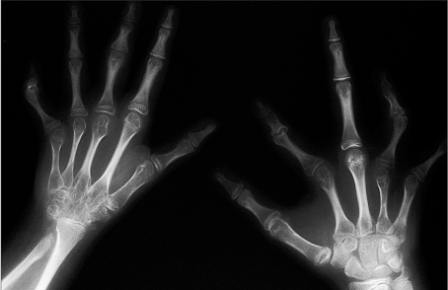

图2-3双手幼年型特发性关节炎

双手诸掌指及指间关节骨质疏松

左手腕骨及掌骨骨质疏松

图2-7幼年型特发性关节炎(晚期)

11岁,双手数个掌指关节骨质侵蚀破坏,关节间隙狭窄,部分指间关节亦明显狭窄,右手第二指远侧指间关节半脱位(形成偏移畸形),腕骨融合

图2-8幼年型特发型关节炎(晚期)

12岁,双多个关节间隙狭窄,融合,其中多个关节偏移畸形。右腕骨明显骨质疏松,多个腕掌关节融合。右尺骨远端畸形,桡骨远端亦发育不好,系骨骺早闭所致